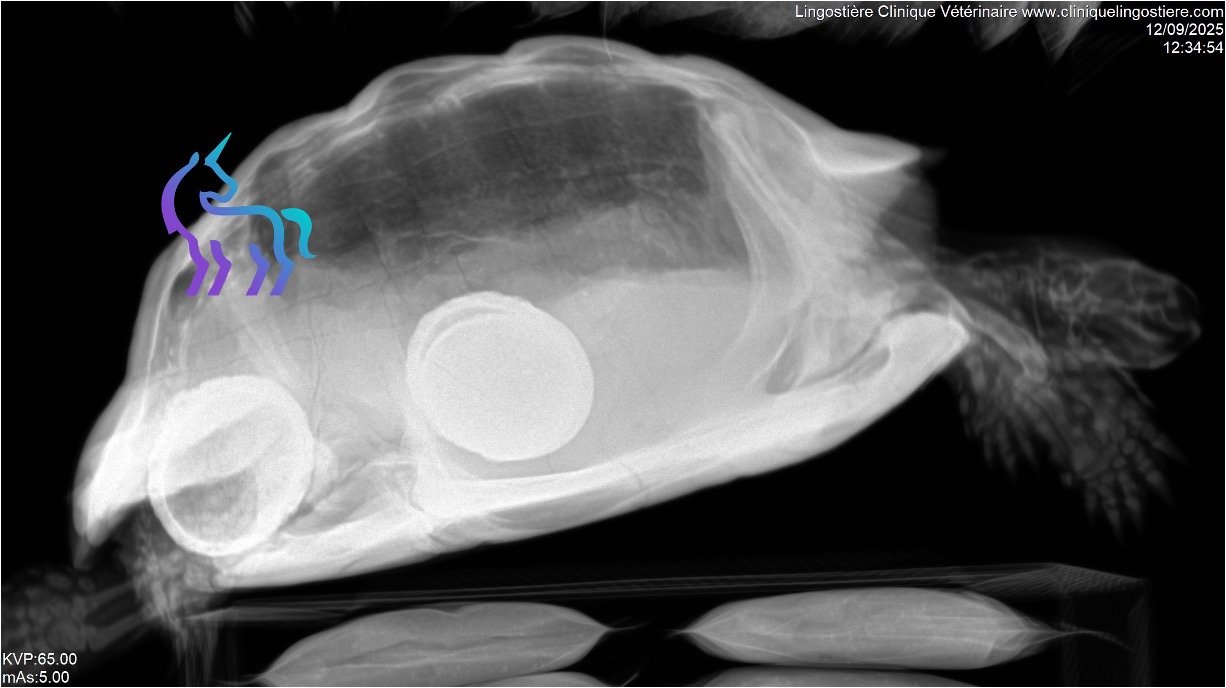

Rétention d’œufs chez la tortue (Dystocie) : causes et traitements

La rétention d’œufs post-ovulatoire est une pathologie fréquente chez les femelles tortues en captivité. Bien que son diagnostic soit rapide via imagerie, il est impératif d’identifier les causes profondes pour garantir la survie de l’animal.

Traitement chirurgical : la plastrotomie

En cas d’échec du traitement médical ou si la tortue présente des signes de septicémie ou d’obstruction, l’intervention chirurgicale devient vitale : l’Ovario-salpingectomie par plastrotomie.